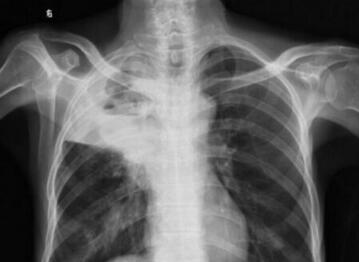

早产儿吞咽反射不成熟,吞咽动作不协调,易发生乳汁吸入。脑部损伤或颅神经病变也可使吞咽反射迟钝或不全,乳汁在咽部排空时间延长。有时咽部神经肌肉不协调,吞咽时乳汁部分进入食管,部分由鼻腔流出,部分吸入呼吸道,而引起肺炎。

当乳汁吸入肺泡后,肺组织出现炎症反应,数小时后有中性粒细胞、吞噬细胞和红细胞渗出,肺泡壁增厚,间质炎症明显,数周后出现纤维化,如反复吸入,可呈慢性间质性肺炎。